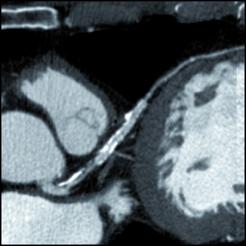

Visit nuffield health for more not everyone needs ct calcium scoring. Another name for this test is coronary artery calcium scoring. The more calcium in your arteries, the more likely you are to have heart disease.

Cardiac calcium scoring can detect calcium deposits before they get large enough to obstruct the blood.

Specifically, it looks for calcium deposits in the coronary arteries that can narrow arteries and increase the risk of heart attack. The calculated agatston score allows for an early risk stratification of patients with a high agatston score (>160) have an increased risk for a major adverse cardiac event (mace) 4. Cardiac ct for calcium scoring. I got my results today.